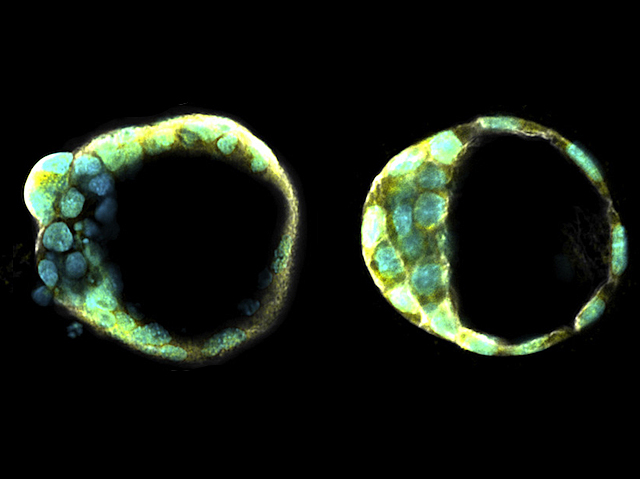

Life's a Blast

The earliest stage after fertilisation emulated in the lab

Life begins with limitless potential. Sperm fertilises egg, and the product then divides to form two cells that have the capacity to ultimately develop into any type of cell. This ‘totipotent’ state is tantalising to researchers interested in regenerative medicine, as it could allow the regrowth of any material in the body, but encouraging cells into this super flexible state is hard. When developing cells reach the womb, they have formed a hollow ball structure – a blastocyst with cells destined to form the placenta on the outside, and totipotent cells inside. Now researchers have artificially created a blastocyst-like structure (left, compared to an actual blastocyst, right, stained to highlight DNA and other molecules). Though not yet a perfect replica, it prompted pregnancy-related changes when implanted in a mouse's womb, raising hopes that it could prove useful for fertility research, and might be a step forward for regenerative medicine.